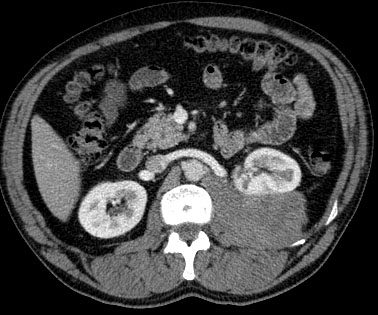

CASO 1: Paciente de 58 años que se realiza TC de abdomen tras historia de dolor abdominal y hematuria microscópica. Refiere pérdida de peso en las últimas semanas.

Estamos ante una afectación bilateral del espacio perirrenal, más evidente en el lado derecho, por masas de densidad de partes blandas en un paciente con numerosas adenopatías retroperitoneales. Estaría indicado realizar una biopsia, ya que el diagnóstico principal orienta hacia un síndrome linfoproliferativo, espcialmente linfoma no Hodgkin tipo B.

2. LINFOMA.

El linfoma renal presenta una gran variedad de manifestaciones. Entre un 3 y un 8 % de linfomas estudiados por TAC tienen afectación renal o perirrenal, más frecuentemente el tipo no Hodgkin.

Patrones de afectación del linfoma renal:

- Multiples masas renales en el riñón (+frecuente)

- Lesión solitaria.

- Adenopatías retroperitoneales con extensión directa a riñón y EPR (nuestro caso de hoy).

- Afectación del espacio perirrenal aislada.

- Infiltración difusa de uno o ambos riñones.

En el caso de que el linfoma afecte al EPR, se ve como una masa homogénea que ocupa este espacio y que desplaza el riñón hacia adelante, ocupando a menudo también el espacio pararrenal anterior. La afectación aislada del EPR por el linfoma es poco frecuente (<10%), es más común la extensión directa desde las adenopatías o grandes conglomerados/masas retroperitoneales (+frec) o la extensión desde el riñón.